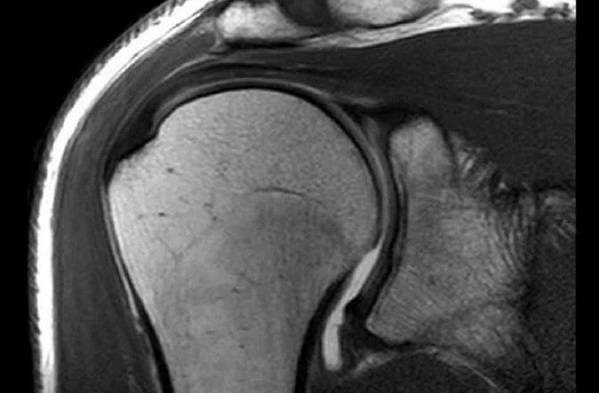

Плечевой сустав на МРТ